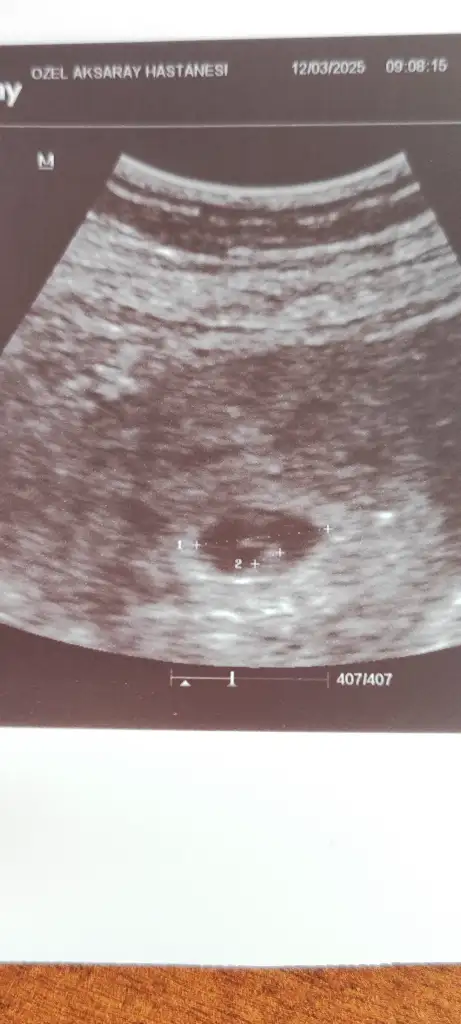

Lütfen banada bakarmısın Pasha22 Pasha22

Vajinal ilk 6 hafta

Ikinci 11 hafta

Eklentiler

• 1000206281.webp

1000206281.webp

8,9 KB · Görüntüleme: 52

• 1000217629.webp

1000217629.webp

15,9 KB · Görüntüleme: 52